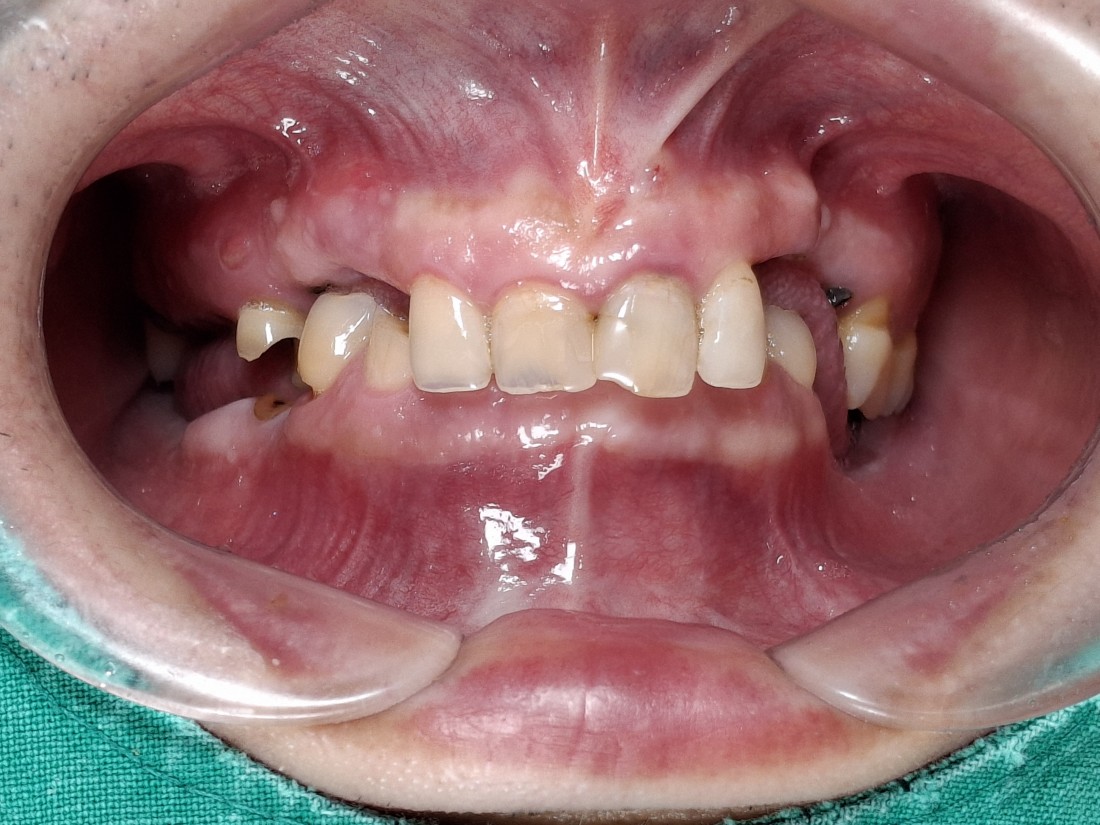

수완동 임플란트 치과는

수 백개의 임플란트 전/후 케이스 사진을

홈페이지에 공유하고 있습니다.

전체 임플란트부터

신경쓰이는 앞니 임플란트,

20대 / 30대 임플란트 케이스부터

80대가 넘는 분들의 케이스까지

정말 다양한 모든 케이스를 보유하고 있습니다.

다양한 각도의 임플란트 식립 전/후 사진으로

실력에 자신있는

수완동 임플란트 치과입니다.